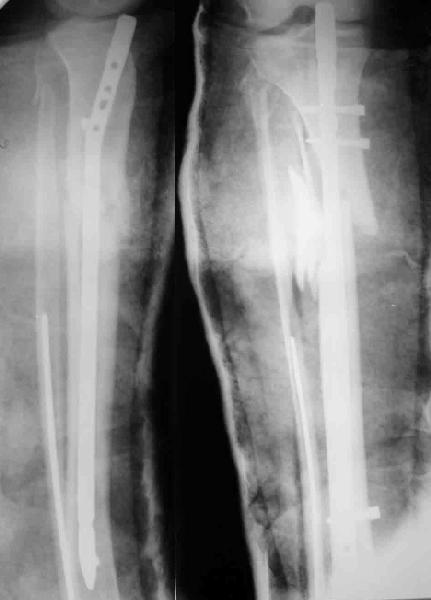

Декабрь 2003 22 июня 2004

В декабре прошлого года обсуждался случай бамперного перелома голени, когда молодой женщине в одной из больниц Москвы неудачно был выполнен остеосинтез гвоздем - это обсуждение можно просмотреть здесь, снимок тогдашний прилагаю.

Вчера поступила к нам в отделение. Клинически определяется приличная подвижность, градусов 35 в переднезаднем направлении. На снимках еще видны фиксированная тоникм стержнем уже сросшаяся малоберцовая кость, и тоже сросшийя перелом дистального метадиафиза большеберцовой кости без признаков хирургической фиксации (?). Сегодняшний снимок также в приложении.